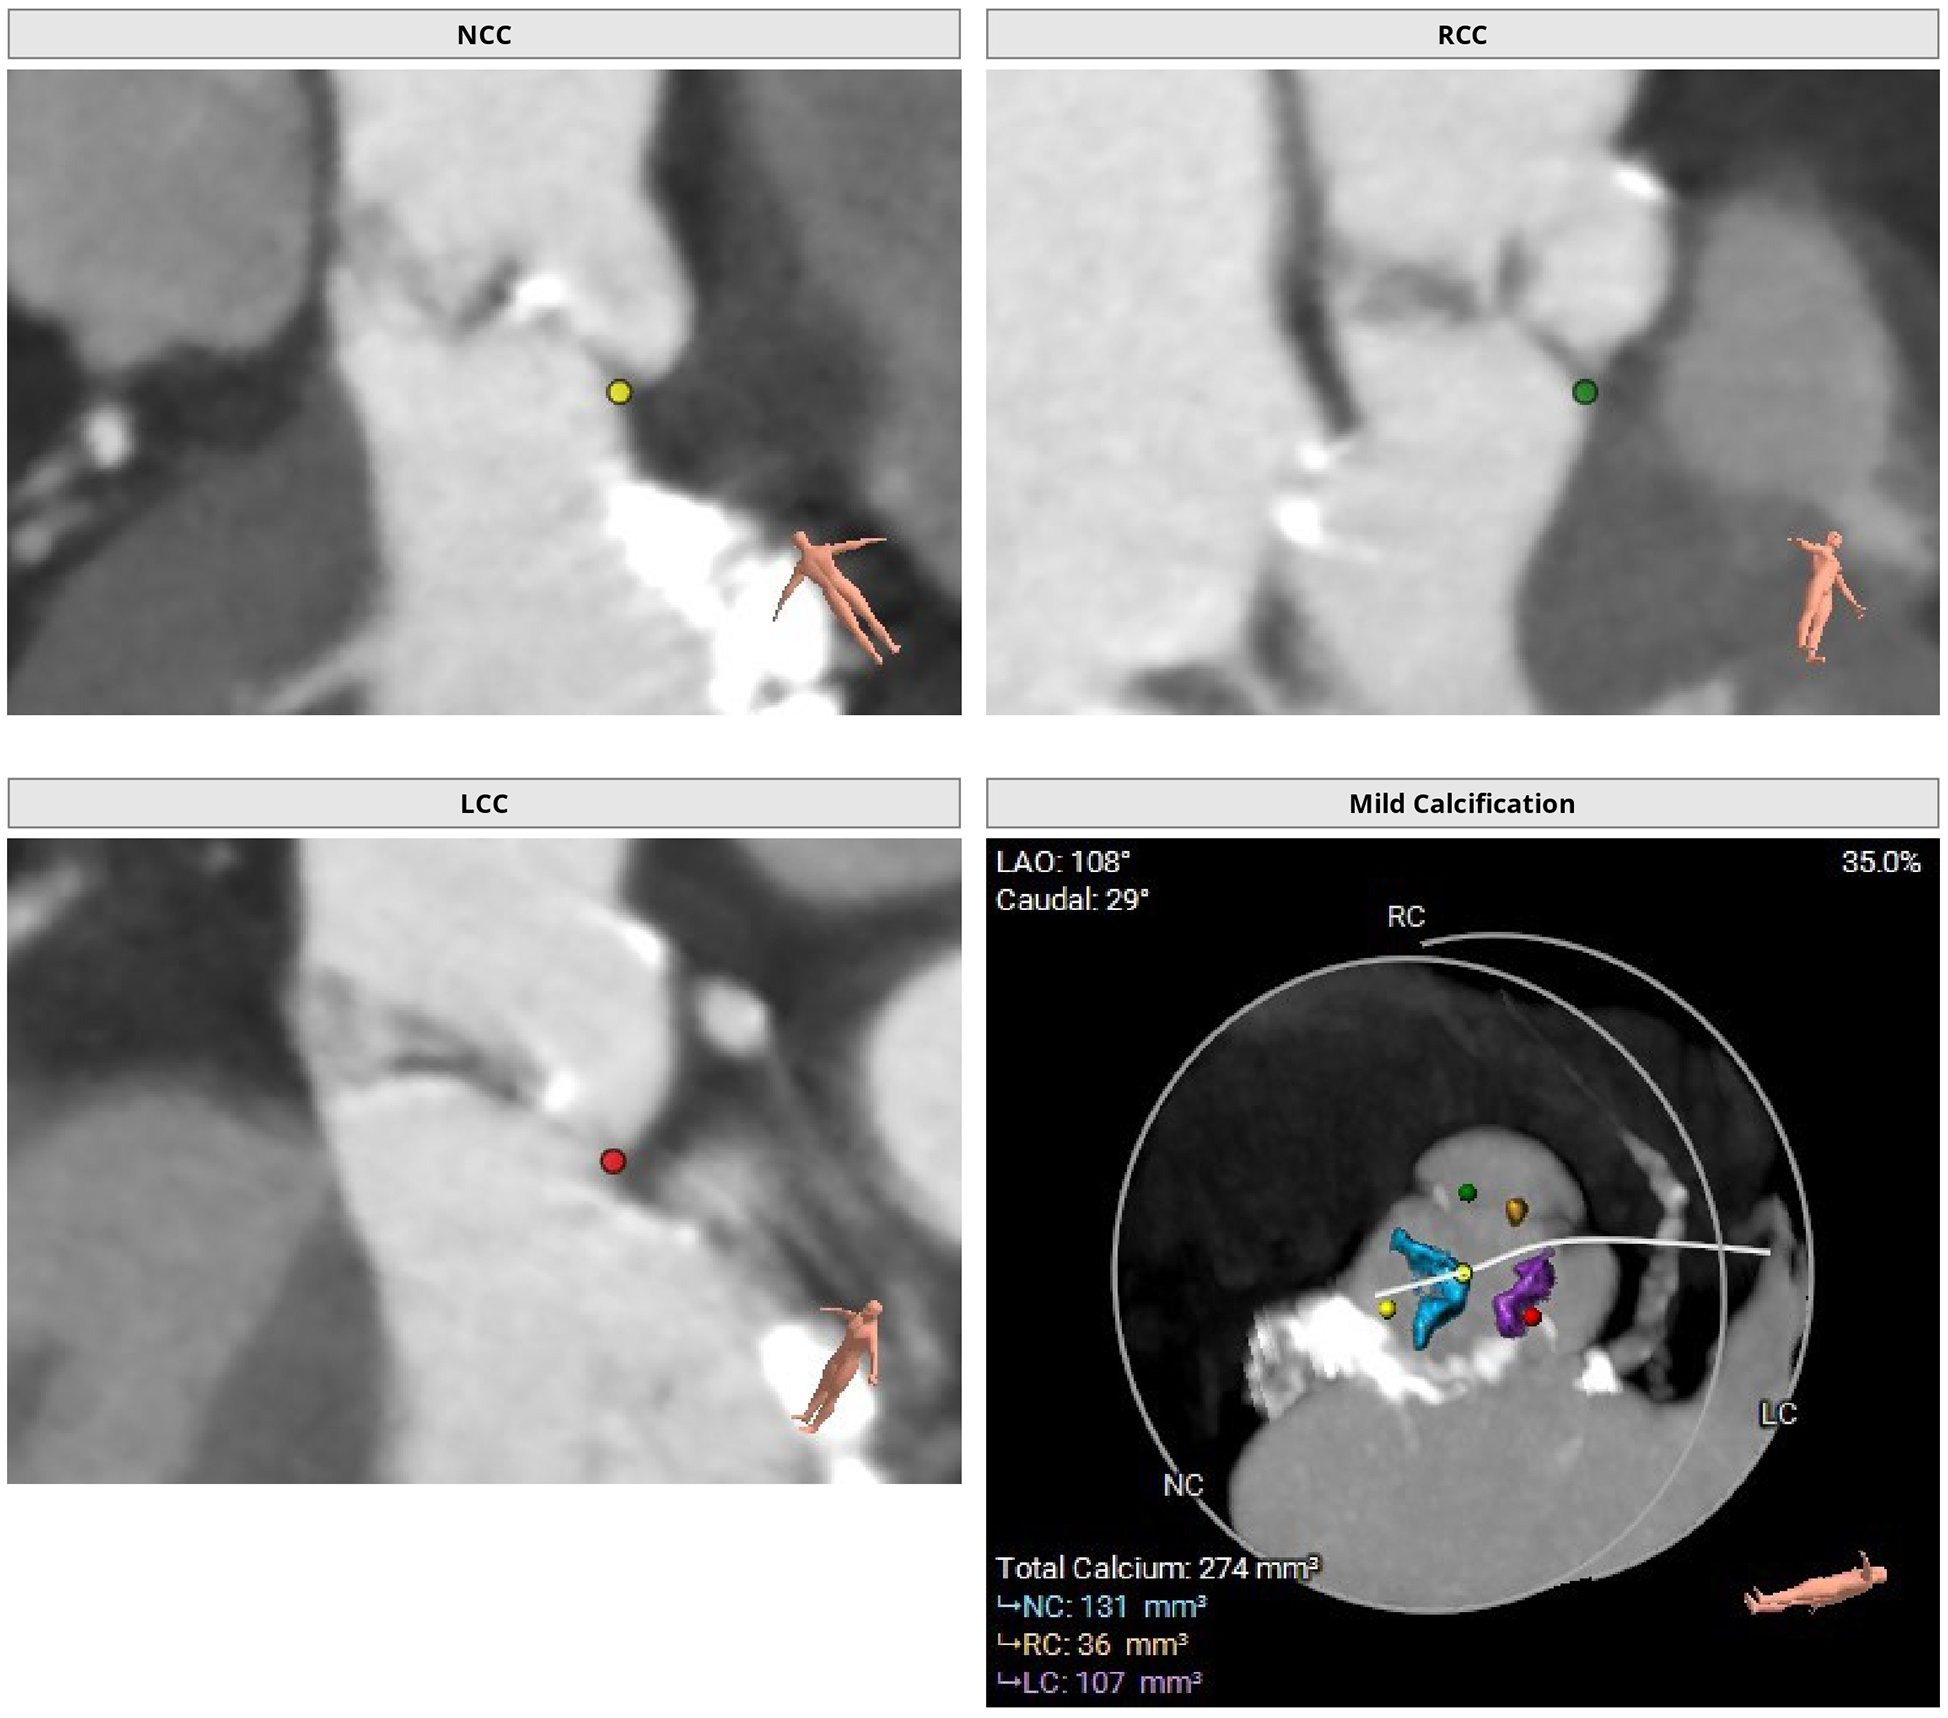

Figure 1

Preoperative thoraco-abdominal CT images were analyzed using 3mensio Structural Heart software (Pie Medical Imaging, the Netherlands). Preoperative thoraco-abdominal CT images showed a tricuspid aortic valve with mild valvular calcifications.